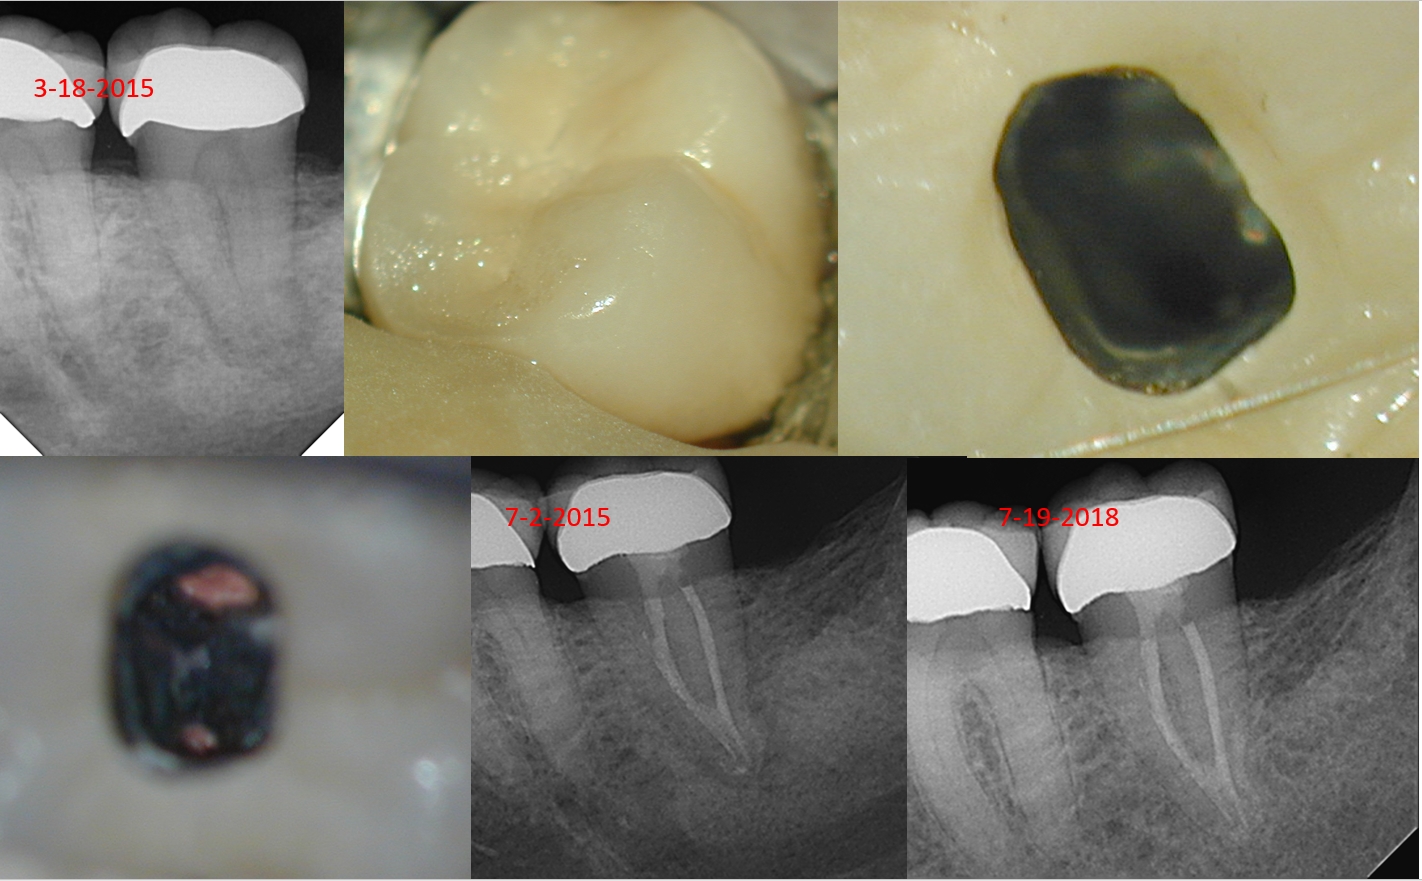

Abscessed pulp on entry. Crown cemented within 6 months of visit to our office. 17/.04 V-Tapers. Three months of Calcium hydroxide with a change in between. Last Radiograph is a 3.5 year recall.

Ah……the fact is almost every C-shaped anatomy has a “missed” canal. Let’s assume you are correct—but we have radiographic resolution—despite what must be billions of microorganisms still present. And trust me, they are still alive.

Hmm…how could that be? Since the patient-centered outcome and the disease-centered outcome appear optimal….well, maybe addressing all the anatomy—the process-centered outcome—isn’t all what it’s cracked up to be?

What you can say about this case is you have an optimal outcome at year 3.5. You can’t draw useful inferences from any one case or even any group of cases unless they follow strict CONSORT guidelines and you follow those cases over a longer time frame. Such guidelines are seldom, if ever, done in endodontics.